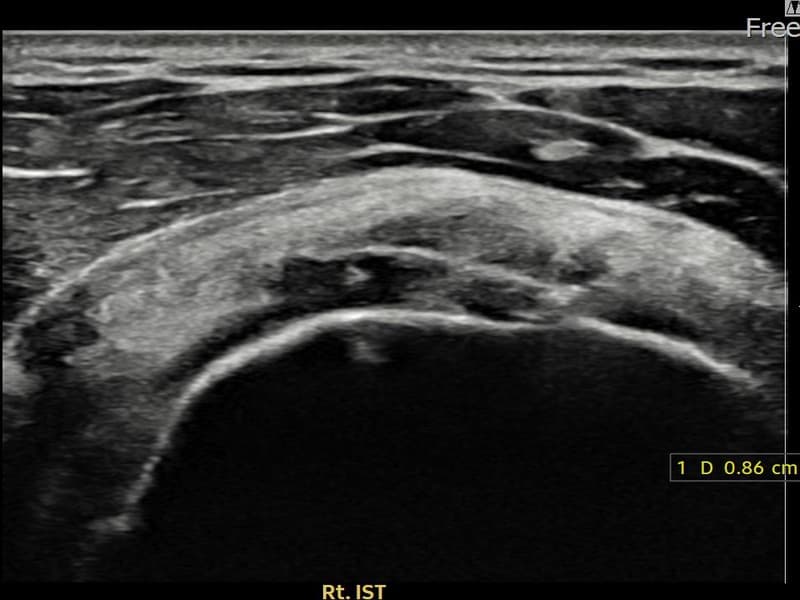

超音波検査にて右 棘下筋腱 関節面側部分断裂(7mm × 3mm (腱厚の約32%欠損))を確認。縫縮術施行後、腱の連続性が回復し、日常生活に復帰されました。

施術前

術前超音波にて右 棘下筋腱 関節面側部分断裂・右肩棘下筋腱のエコー不連続と腱欠損(7mm × 3mm (腱厚の約32%欠損))を確認。術後超音波では断裂部位が再生組織で充填され、腱の連続性回復とエコーパターンの正常化が確認されました。

持続する右肩痛で来院された患者様です。超音波検査にて右 棘下筋腱 関節面側部分断裂(欠損:7mm × 3mm (腱厚の約32%欠損))を確認し、超音波ガイド下で非手術的縫縮術を施行しました。術後は約4〜6週間のブレース装着の後、段階的なリハビリプログラムを実施。経過超音波で腱の連続性回復を確認し、患者様は無事に日常生活へ復帰されました。